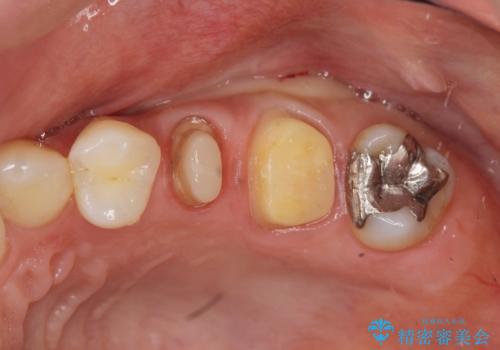

放置し崩壊した歯 セラミック治療による咬合機能回復

- 忙しくて歯科医院に通えず、ついに歯が折れてしまい治療を希望され来院されました。

虫歯を丁寧に除去したのち、なんとか歯を残せる見通しがたったので根管治療を行いセラミック補綴を行いました。